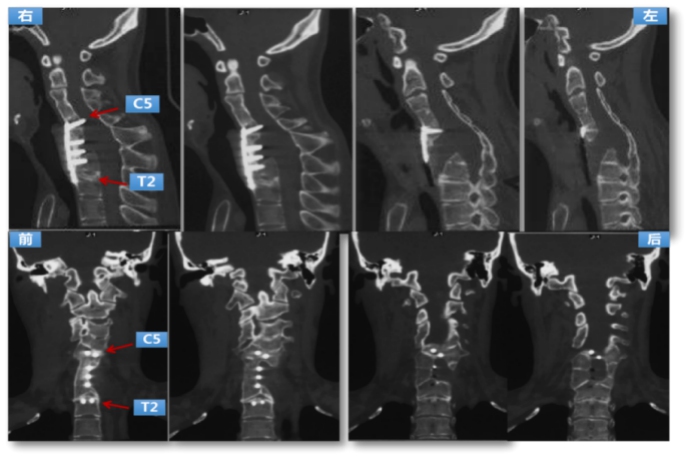

Preoperative CT: the left anterior bone defect of cervicothoracic vertebrae, partial screw’s original nail plate system was cut out before the spinal canal was entered.

Preoperative MRI: the dura mater and spinal cord herniated from the defected bone to the front of the vertebral body to the left, which shows spinal cord compression and ischemic degeneration.

Using digital medical technology plans to simulate the surgery